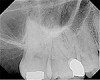

Fig 4. This maxillary first molar was to have endodontic therapy following diagnosis of irreversible pulpitis.

Figure 4

Fig. 5 This maxillary first molar was to have endodontic therapy following diagnosis of irreversible pulpitis.

Figure 5